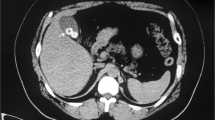

Case 2

A 40-year-old female patient had suffered from upper quadrant abdominal pain, with occasional nausea and fever for more than 2 years. The patient was diagnosed as cholecystitis at another hospital nearby and felt relieved very soon after treatment in the past 2 years. She came to the hospital 11 days ago due to the severe upper quadrant abdominal pain recurred with severe jaundice. Complete medical examinations, including blood pressure, pulse rate, temperature and physical examination of the abdomen, were performed in the Fifth Affiliated Hospital of Sun Yat-sen University. The clinical examinations revealed that the pulse rate, temperature and blood pressure were normal. Stool microscopy for parasite eggs by direct smear method were negative 3 times. Computed tomography (CT) scan revealed obstruction of the bile duct with dilation of the intrahepatic ducts which suggested a retained bile duct stone and a gallbladder stone (Fig. 3). Laboratory data indicated obstruction jaundice, peripheral eosinophilia and liver enzymes elevation (Table 1). Detailed inquiry revealed she had a history of eating raw freshwater fish. A clinical diagnosis of acute cholangitis and cholecystitis was made and laparoscopic cholecystectomy and laparoscopic common bile duct exploration was performed. Many flat, leaf-like worms appeared under the choledochoscope as deep bile duct cannulation (Fig. 4 and Fig. 5). Besides, many nodules distributed dispersedly among the surface of the liver (Fig. 6). After the operation, the“T” shape catheter was placed in the common hepatic duct to allow patent drainage. The patient was treated with anthelmintic therapy (albendazole: 16 mg/kg/day for 4 days). More C. sinensis worms were drained through the “T” shape catheter (Fig. 7). The clinical status of the patient improved gradually without the pain recurring.

Fig. 3

Dilation of the intrahepatic ducts by CT scan